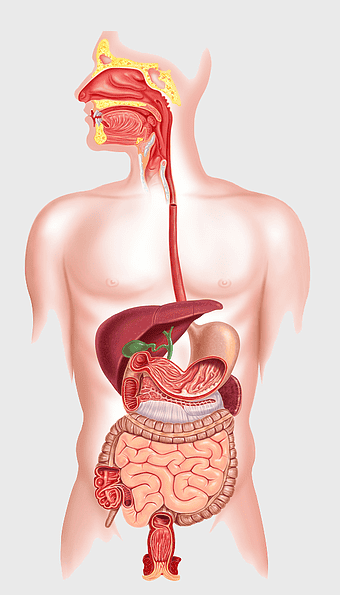

human digestive system, gastrointestinal tract anatomy, liver function, stomach and intestines, digestive health, internal organs diagram, human body systems -

female human organ model, human digestive system anatomy, gastrointestinal tract illustration, liver and stomach diagram, medical education visuals, anatomical study aids, human body internal structures -

human anatomy diagram, digestive system illustration, human internal organs, Homo sapiens muscular system, anatomical art for education, systemic physiology chart, medical biology graphics -

human digestive system illustration, gastrointestinal tract diagram, human body organ system, labeled digestive system, digestive anatomy chart, human internal organs, alimentary canal visualization -

human anatomy illustration, human organ system diagram, human body internal organs, human digestive system, anatomical chart, medical illustration, physiological diagram -

human digestive system anatomy, gastrointestinal tract illustration, stomach muscular layer, abdominal organ diagram, digestive health education, medical biology study, internal human body structures -